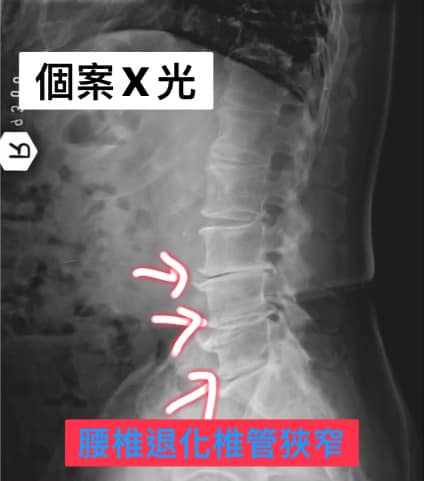

Cervical Spine Treatment Cases 腰椎治療案例 #曾經大痛到送台大急診連打兩支止痛針#椎間盤突出痛到完全無法工作#訪六週密集治療... 2020.09.26 好到症狀完全消失!差點淚灑診間。 2020.09.25 #感謝花蓮鄉親林大姐熱情見證 #腰椎滑脫合併椎管狹窄的病痛 #原本都想去當地開刀了 #... 2020.09.22 #破紀錄了96歲老太爺從新竹北上就醫 #腰椎滑脫合併骨質疏鬆 #原本應該開刀手術但心臟... 2020.09.08 #感謝泰山張阿姨熱情見證 #腰椎滑脫合併椎管狹窄 #原本預定八月中動刀 #逆轉勝成真 #... 2020.09.17 #今天來聊巨大骨刺為何可以吸收回去! #椎間盤突出需要多久才能吸收呢? #馬尾神經症候... 2020.09.08 #典型假性坐骨神經痛 #原來是梨狀肌症候群 #核磁共振排除椎間盤突出 #抽絲剝繭真相大... 2020.08.13 #嚴重椎管狹窄醫案 #感謝台北林大哥熱情見證 #從寸步難行到輕快漫步 #鍛鍊多裂肌的重... 2020.08.12 #椎間盤突出可以吸收回去嗎 #微針治療原理是什麼 #何時一定要接受神外開刀 #一張圖秒... 2020.08.11 #感謝花蓮鄉親林大姐熱情見證 #一分鐘認識椎管狹窄 #原本痛到無法走路打算開刀了 #脊... 2020.08.01 #感謝新莊區林先生熱情見證 #椎間盤突出跟纖維環裂隙的關係 #纖維環破裂突出可以不... 2020.07.28 #逆轉勝又一發case #原本疼痛一年多想說一定要手術治療了 #八週治療後症狀全部消失 #... 2020.07.25 #巨大椎間盤突出一定要開刀嗎 #除了開刀以外的選擇 #感謝台北市吳先生熱情見證 2020.07.24 #腰椎滑脫的疼痛心酸誰人知啊 #一分鐘瞭解腰椎滑脫 #哪一種情況需要積極開刀 #要如何... 2020.07.21 #巨大椎間盤脫垂一定要開刀嗎? #感謝新店林先生熱情見證受訪 #西醫手術有那些選擇... 2020.07.02 ← 上一頁 9 10 11 12 13 下一頁 →